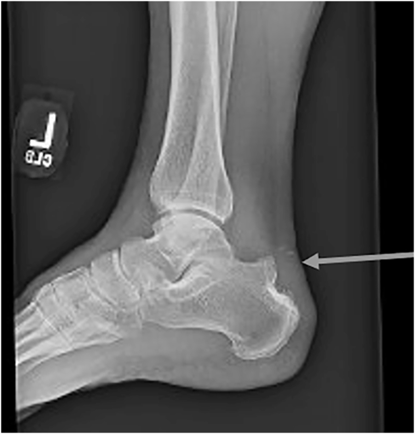

The plain film shows a small, crescent shaped bone fragment adjacent to the lateral tibial plateau.

This fracture is called a Segond fracture

It represents a bony avulsion of the anterolateral ligament (ALL) NOT the ACL

However, this fracture pattern is associated with a tear of the ACL tear 75-100% of the time.

Also associated with meniscal injuries (65-75%)

The ALL runs from the lateral femoral condyle and inserts on the anterolateral proximal tibia near the fibular head

The ALL helps to control tibia internal rotation

Works in concert with the ACL to prevent anterior rotational tibia subluxation

This injury pattern on plain film indicates a significant ligament injury and changes management because ACL reconstruction is often required.